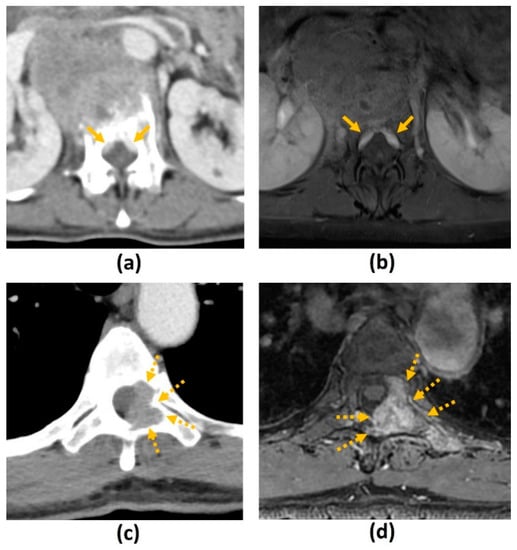

| T2-W | Evaluation of spinal cord and nerve root compression (‘myelogram-like effect’); Detection of cord signal changes (e.g., myelomalacia or oedema) | Suboptimal for evaluation of marrow replacing lesions |

| T1-W | Identification of marrow replacing lesions including metastasis; Useful for comparison with post-contrast sequences to identify true contrast-enhancement | Suboptimal for evaluation of spinal cord and nerve root compression; Peritumoural oedema may also appear hypointense on T1-W sequences, which may limit the accuracy of measurement of the true tumour size |

| T1-W post-contrast FS | Detection of enhancing vertebral metastasis, sites of leptomeningeal and intramedullary disease; Delineation of tumour extent including identification of the epidural component, and presence of foraminal or paraspinal extension; Determination of biopsy site of highest yield (if biopsy required) | Suboptimal for evaluation of spinal cord and nerve root compression |

| STIR | Identification of marrow replacing lesions including metastasis; More accurate measurement of true tumour size from surrounding peritumoural oedema than T1-weighted sequences; Identification of macroscopic fat in lesions | Suboptimal for detection of sclerotic vertebral metastasis without oedema |